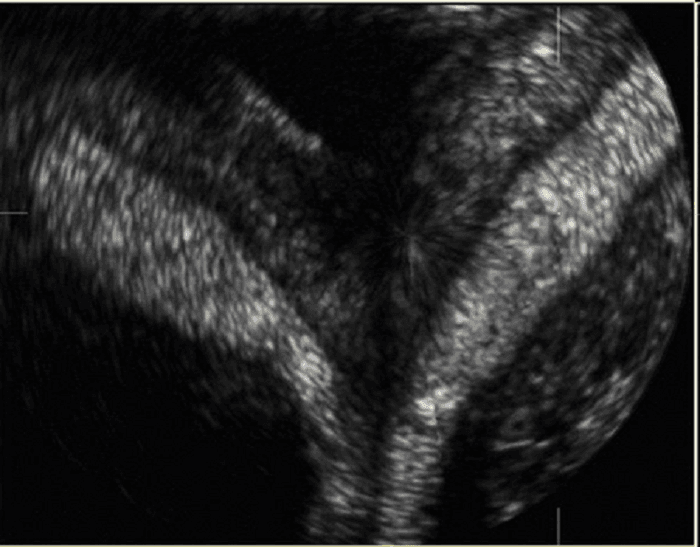

Siêu âm buồng trứng đa nang phát hiện và loại bỏ

Siêu âm buồng trứng đa nang là một trong những xét nghiệm được sử dụng để chẩn đoán hội chứng này. Buồng trứng đa nang có thể hỗ trợ điều trị hiệu quả nếu được phát hiện và loại bỏ. Nhưng đây là bệnh rất nguy hiểm, có thể ảnh hưởng đến sức khỏe và khả […]